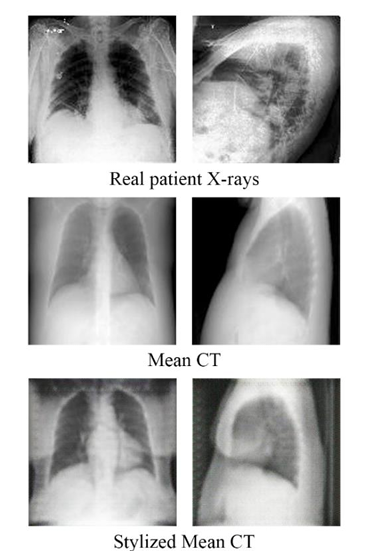

- CycleGAN을 활용하여 Mean CT 이미지를 실제 X-ray style로 변환하는 과정을 추가하였습니다. 또한 기존 CycleGAN에서 학습률을 낮추었습니다.

- CycleGAN의 스타일 재구성 정확도를 높이기 위해 Lambda 값을 10에서 20으로 증가시켰습니다. Lambda는 사이클 일관성 손실을 조절하는 변수로, 값을 높이면 스타일 변환 시 원본 이미지와의 정렬이 개선되었습니다. 하지만 값이 25를 초과하면 style transfer 효과가 약해지는 문제가 발생했습니다. Lambda 값을 20으로 설정했을 때, CT와 비교해 differnt depth가 낮은 X-ray의 특성을 유지하면서도 원본과 유사한 형태를 재현할 수 있었습니다.